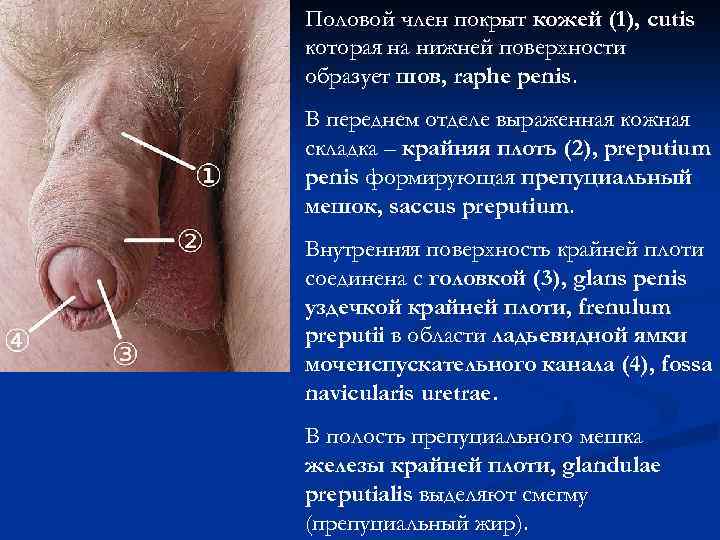

Половой член покрыт кожей (1), cutis которая на нижней поверхности образует шов, raphe penis. В переднем отделе выраженная кожная складка – крайняя плоть (2), preputium penis формирующая препуциальный мешок, saccus preputium. Внутренняя поверхность крайней плоти соединена с головкой (3), glans penis уздечкой крайней плоти, frenulum preputii в области ладьевидной ямки мочеиспускательного канала (4), fossa navicularis uretrae. В полость препуциального мешка железы крайней плоти, glandulae preputialis выделяют смегму (препуциальный жир).

Половой член покрыт кожей (1), cutis которая на нижней поверхности образует шов, raphe penis. В переднем отделе выраженная кожная складка – крайняя плоть (2), preputium penis формирующая препуциальный мешок, saccus preputium. Внутренняя поверхность крайней плоти соединена с головкой (3), glans penis уздечкой крайней плоти, frenulum preputii в области ладьевидной ямки мочеиспускательного канала (4), fossa navicularis uretrae. В полость препуциального мешка железы крайней плоти, glandulae preputialis выделяют смегму (препуциальный жир).